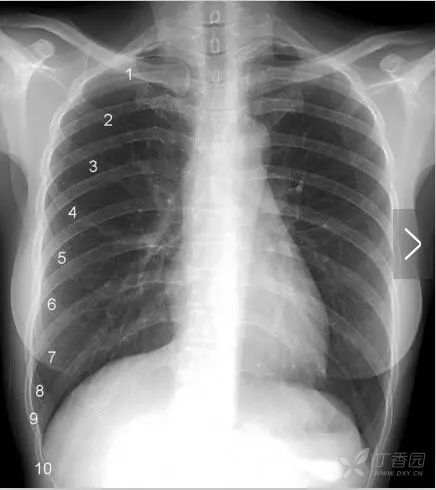

肋 骨 一根肋骨在正位胸片上投影的前后端并不在同一水平,为了便于描述,肋骨被人为的分为后段(后肋)和前段(前肋)两个部分。后段通常是肋骨从胸椎到肺野外缘的投影,走行大致水平或略向外下倾斜。前段从肺野边缘起向内下呈比较大角度的斜向走行,越是接近第11、12肋的肋骨,其前段向下倾斜的角度越大。

图中1~10分别标示第一到第十前肋。